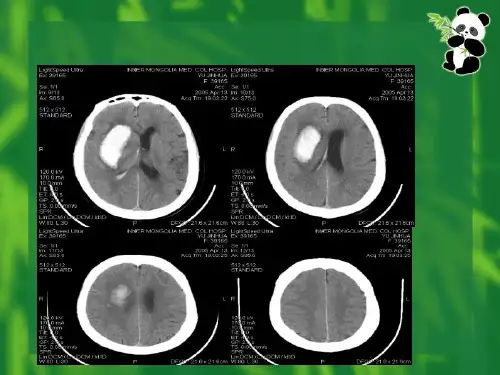

颅内血肿穿刺定位法(ppt)